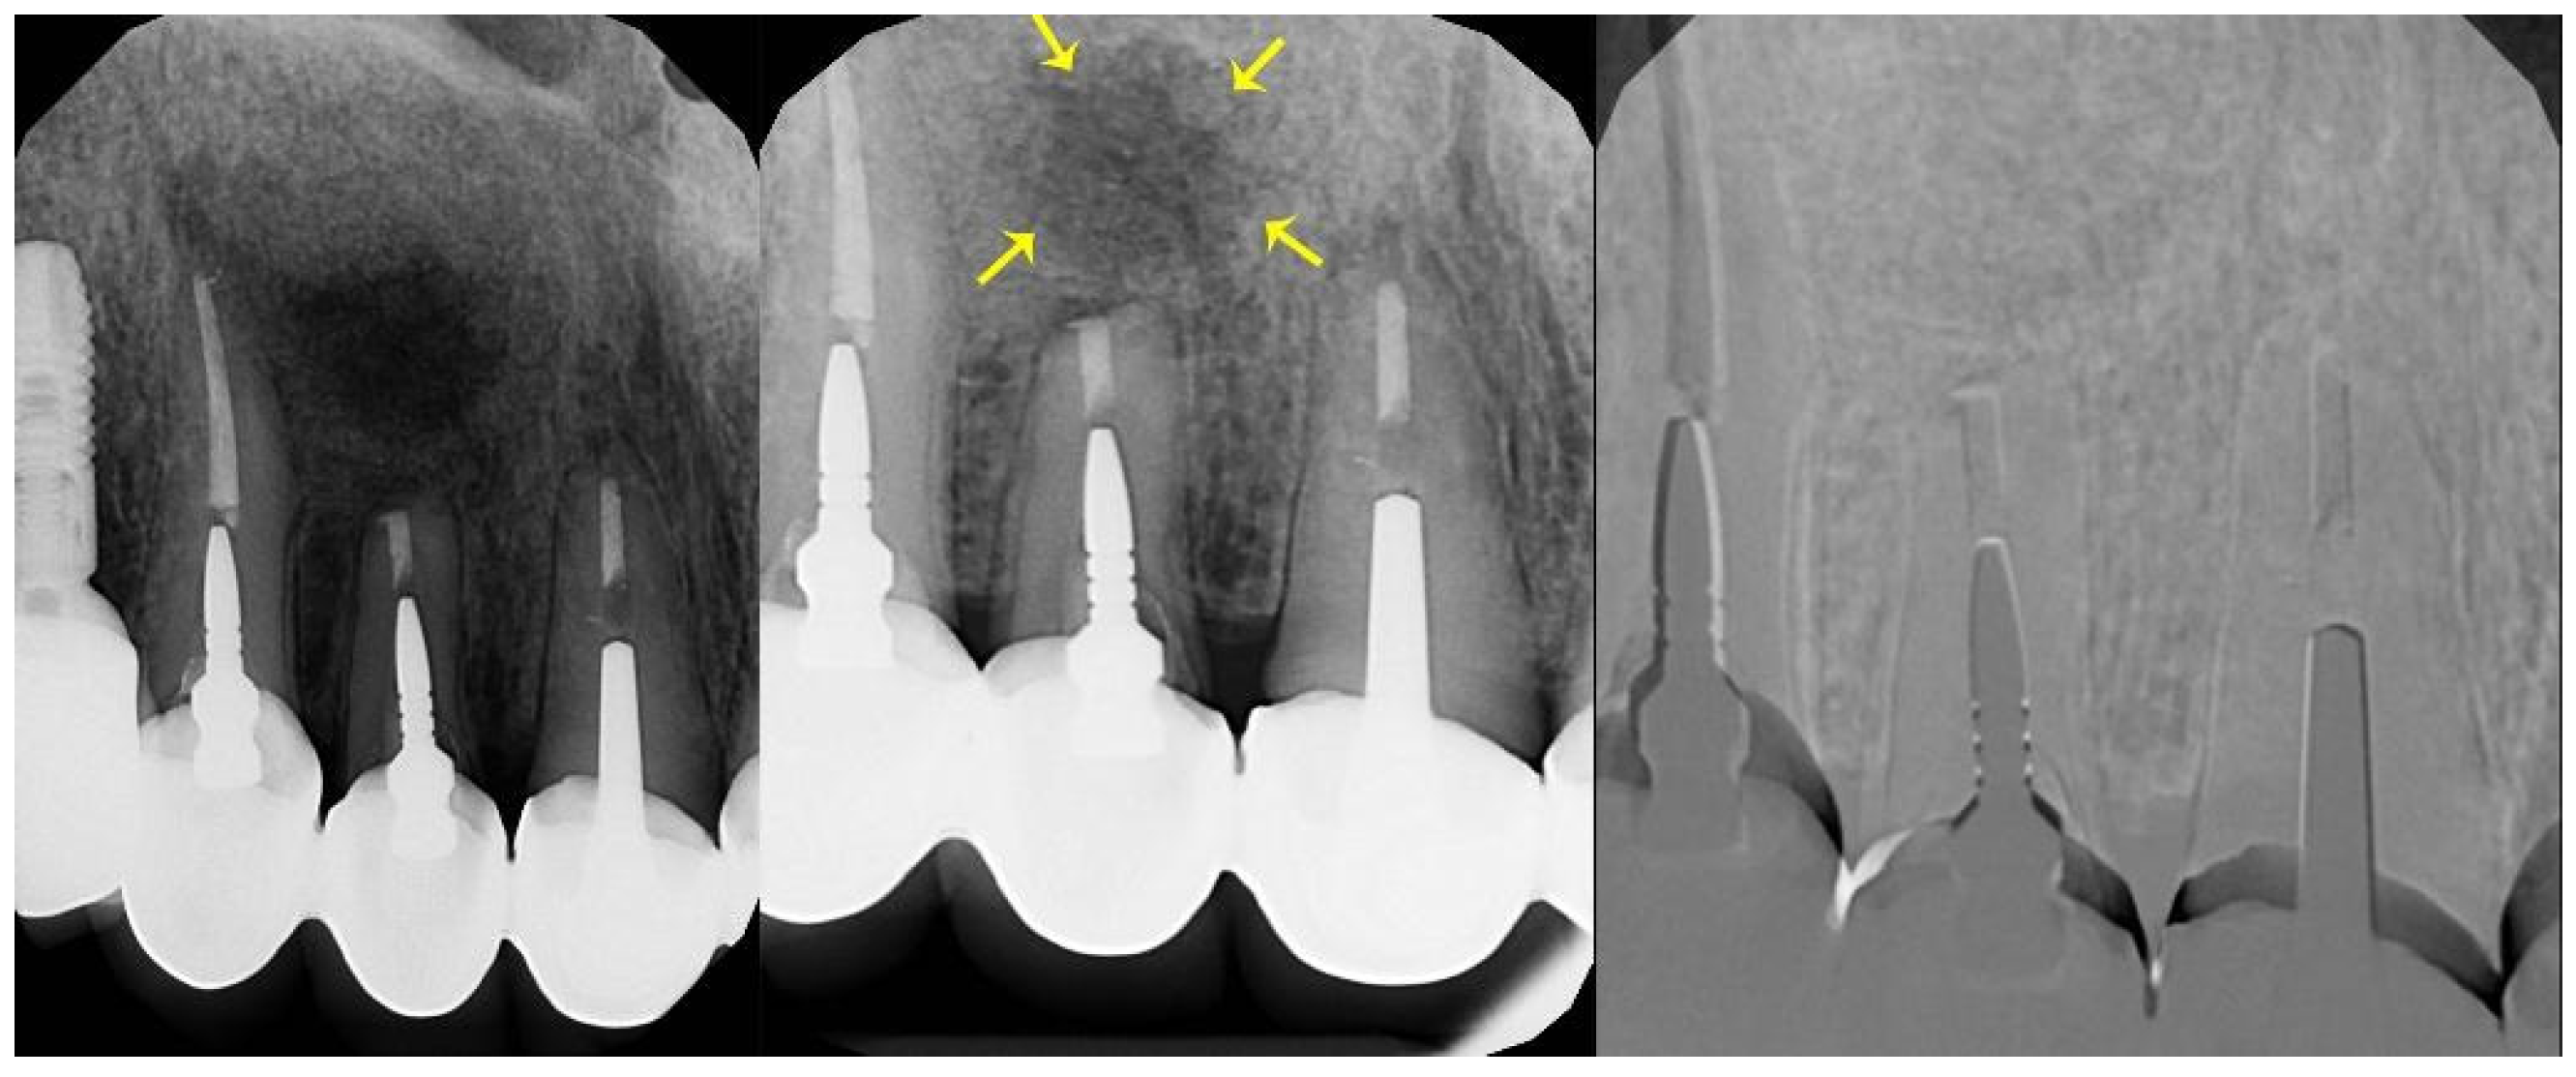

| Postoperative (mean mm ± SD) | 17.97 ± 4.98 | 18.4 ± 6.56 |

| 6-month follow-up (mean mm ± SD) | 16.69 ± 4.53 | 18.11 ± 6.53 |

| 12-month follow-up (mean mm ± SD) | 15.23 ± 3.67 | 17.66 ± 6.52 |